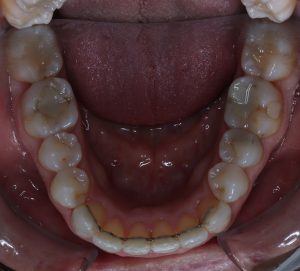

INITIAL

22 Semanas de Tratamiento